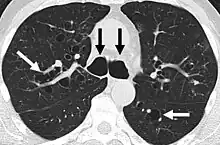

A chest x-ray is abnormal in most patients with bronchiectasis. Computed tomography is recommended to confirm the diagnosis and is also used to describe the distribution and grade the severity of the disease. Radiographic findings include airway dilation, bronchial wall thickening, and atelectasis.[66] There are three types bronchiectasis that can be seen on CT scan, namely cylindrical, varicose, and cystic bronchiectasis.[67]

Bronchiectasis primarily in the middle lobe of the right lung.

Bronchiectasis secondary to a large carcinoid tumor (not shown) that was completely obstructing the bronchus proximally. Dilation of the airways is present.